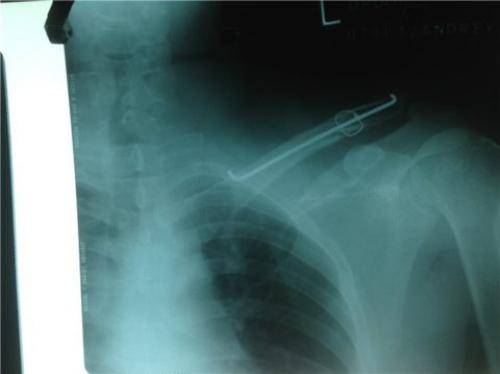

Фиксация ключицы спицами при остеосинтезе

Соединение отломков спицами

Спицами проводят остеосинтез ключицы с целью соединения фрагментов кости при переломе довольно редко, поскольку после операции они мигрируют, изгибаются и ломаются.

Посредством небольшого разреза кожи с помощью электросверла формируют ход и затем туда забивают стержень и соединяют отломки. После придают им физиологическое положение и кетгутовыми нитями фиксируют, рану – наглухо послойно зашивают.

Только потом накладывают шину из гипса и фиксируют конечность на клиновидной подушке. Стержни удаляют спустя 1.5-2,5 месяца после остеосинтеза. Восстанавливается ключица при правильном лечении 6-7 недель. Постепенно стихают боли и отек, формируется костная мозоль, которая соединяет костную ткань.